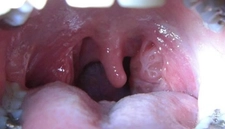

2. EnfeksiyonlarBoğaz yanması, özellikle enfeksiyonlar sonucunda da sıkça görülebilir.

3. AlerjilerAlerjik reaksiyonlar, boğazda yanma hissine neden olabilmektedir.

4. Sigara ve Alkol KullanımıSigara içmek ve aşırı alkol tüketimi, boğazın tahriş olmasına neden olabilir.

5. Kimyasal TahrişKimyasal maddeler, boğazda yanma hissine neden olabilen önemli bir faktördür.